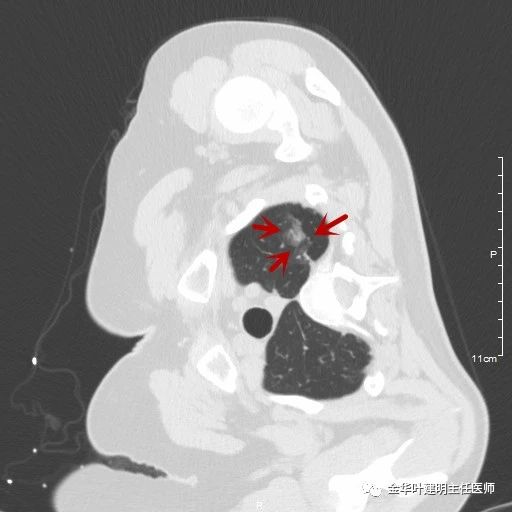

傅某,57岁,于今年9月份时因腹痛在我院外科住院,当时查胸部CT平扫发现左肺尖混合磨玻璃结节,平扫图像如下:

可见是左肺尖混合磨玻璃结节,长径约2.5厘米许,瘤肺边界清晰,特别是后侧,靠近内侧部分密度较高,以致病灶呈混合磨玻璃影像特点。我们再来看其靶扫描图片:

红色箭头示病灶,绿色箭头示实性成分,再靠胸壁处是肺尖纤维条索样区域